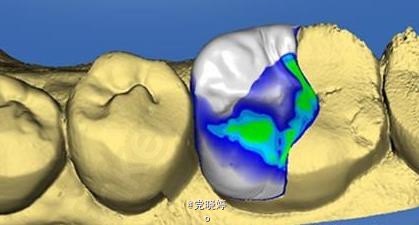

36根管再治疗后E.max瓷嵌体修复

36根管再治疗之后嵌体修复

患者满意,效果很好。